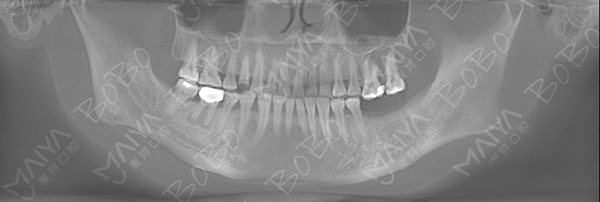

郭女士术前口腔ct全景片

种植牙后口腔内全景片